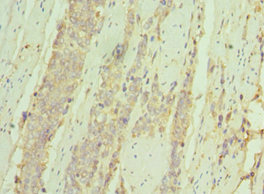

Immunohistochemistry of paraffin-embedded human skin tissue using CSB-PA011670ESR1HU at dilution of 1:100

Immunohistochemistry of paraffin-embedded human colon cancer using CSB-PA011670ESR1HU at dilution of 1:100